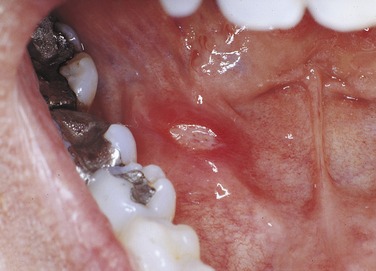

PLATE 12 Minor aphthous ulcer on the buccal mucosa on the papilla of Stensen’s duct.